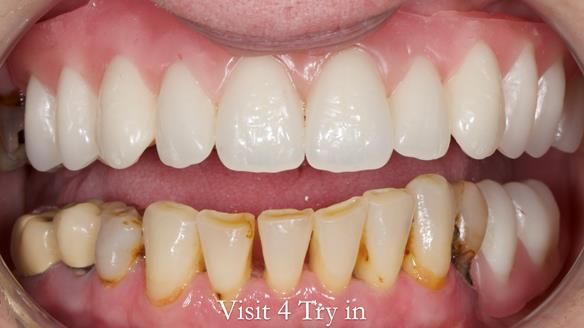

This newsletter describes the full protocol workflow of a complete upper denture and a lower partial denture for Jo.

Findings/diagnoses/observations and discussion points given to the patient following consultation.

- The missing upper front teeth are replaced by a denture made by the patient. This has poor fit and appearance.

- The upper ridge with missing teeth has very little underlying bone.

- The upper natural teeth have hopeless prognosis due to dental caries.

- The LR6, 5, 4 have guarded prognosis because of dental caries.

- The lower front teeth (LR3 – LL3) have better prognosis (although, I think there is high chance of loss – over the next 10 - 15 years). However, I do not believe it is right to remove them as they are in good condition compared with the other teeth and coping with a lower full denture is far more difficult (affecting your quality of life) than a lower metal based partial denture supported by natural teeth as proposed in the treatment plan below.

- The forces placed on the teeth are large (bruxism). This will make the dentures proposed in the treatment plan below wear, chip and break more quickly. Therefore, the final dentures will require metal reinforcement to make them as robust as possible.

- Upper complete denture and lower partial denture along with removal of failing teeth - Jo wanted this

The clinical situation and treatment process is shown in detail below. I provided the clinical work. Rowan Garstang provided the technical work. This treatment took 25 visits over a period of 12 months.